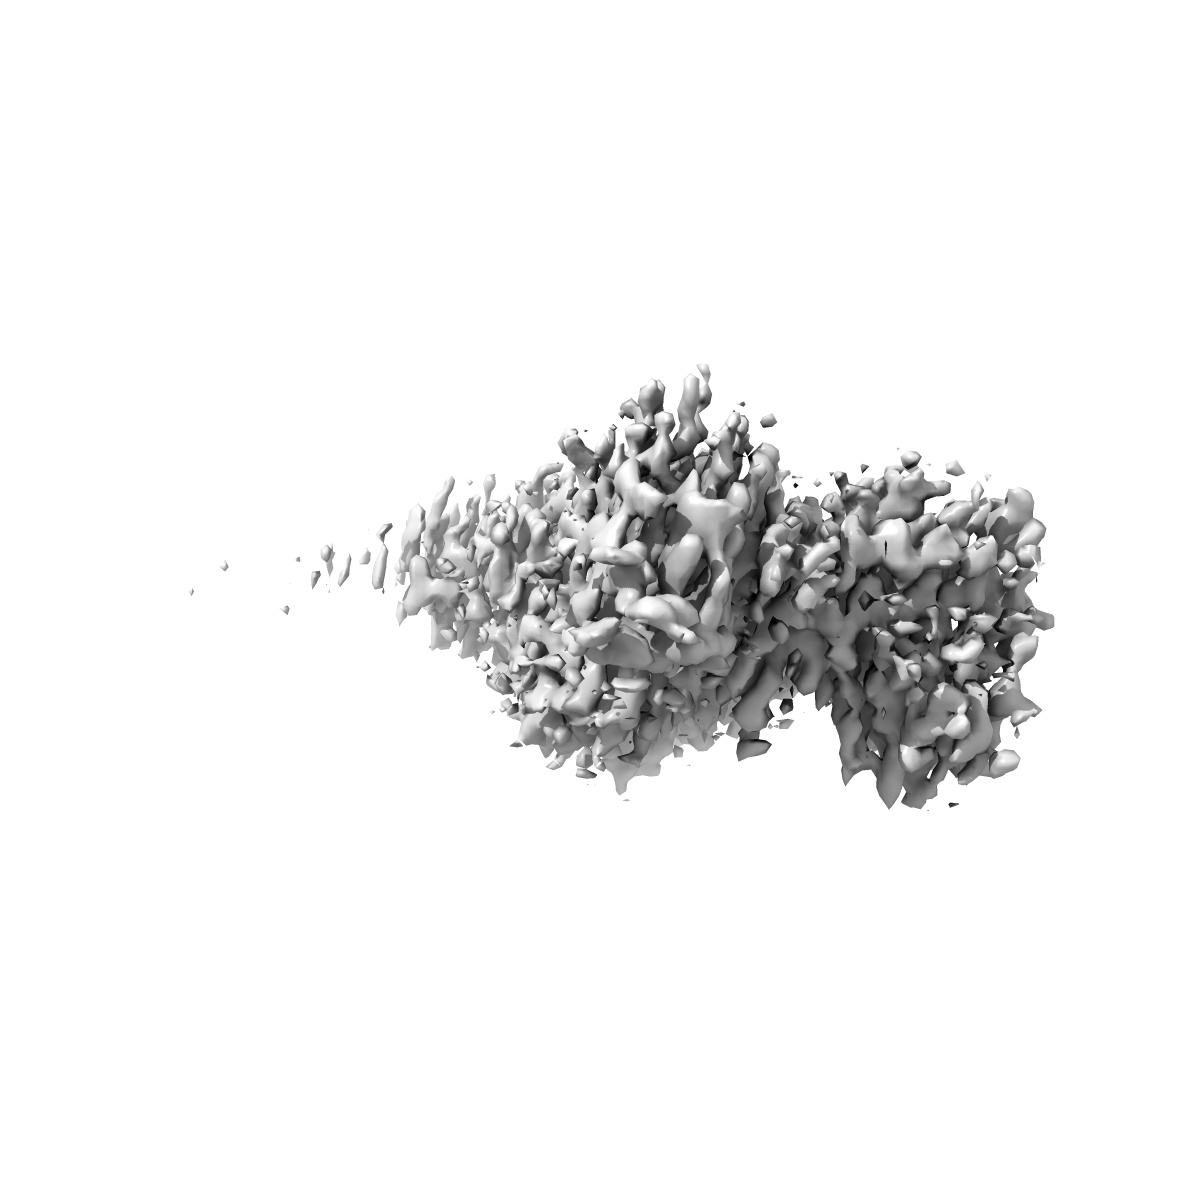

Focused refinement Fab-Nb (cryo-EM structure of inactive human arginine-vasopressin (AVP) V2 receptor (V2R) with Mambaquaretin1 K39A (MQK39A))

Sample: Inactive V2R-bril bound to tolvaptan stabillized with anti-BRIL Fab and anti-BRIL Fab Nanobody

Inactive structures of the vasopressin V2 receptor reveal distinct binding modes for Tolvaptan and Mambaquaretin toxin.

(2025) Nat Commun , 16 , 3899 - 3899